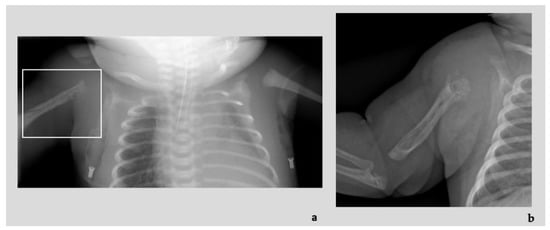

Diagnostic imaging investigations showed the presence of numerous ectatic and tortuous high-flow arterial structures at the level of the vascular malformation of the right upper limb, associated with diffuse osteostructural alteration of the humerus and proximal radius and ulna (Figure 3a,b). At the clinical evaluation at birth, the newborn presented edematous with respiratory distress, heart failure consequent to blood shunt, an overgrown and swollen right limb with skin port-wine stains and subcutaneous pulsatile vascular anomalies (Figure 3c). An echocardiogram also showed dilatation of the superior vena cava and of the right cardiac sections, patent foramen ovale (PFO) with right-left shunt. He was admitted to the neonatal intensive care unit where he was intubated and treated with prostaglandins, steroid and beta-blocker drug therapy with progressive improvement in the clinical features. The vascular malformations were treated with endovascular coil insertion.

Figure 3.

Patient 4: Radiographic images showing destruction and absorption of the proximal epiphysis of the humerus (adjacent to the arteriovenous malformation of the right arm), features indicative of Parkes Weber Syndrome ((a) at birth and (b) at 2 months of life). Proband at birth with overgrown and swollen right limb with skin port-wine stains and subcutaneous pulsatile vascular anomalies (c); proband’s mother capillary malformations on her wrist and shoulder (d,e).